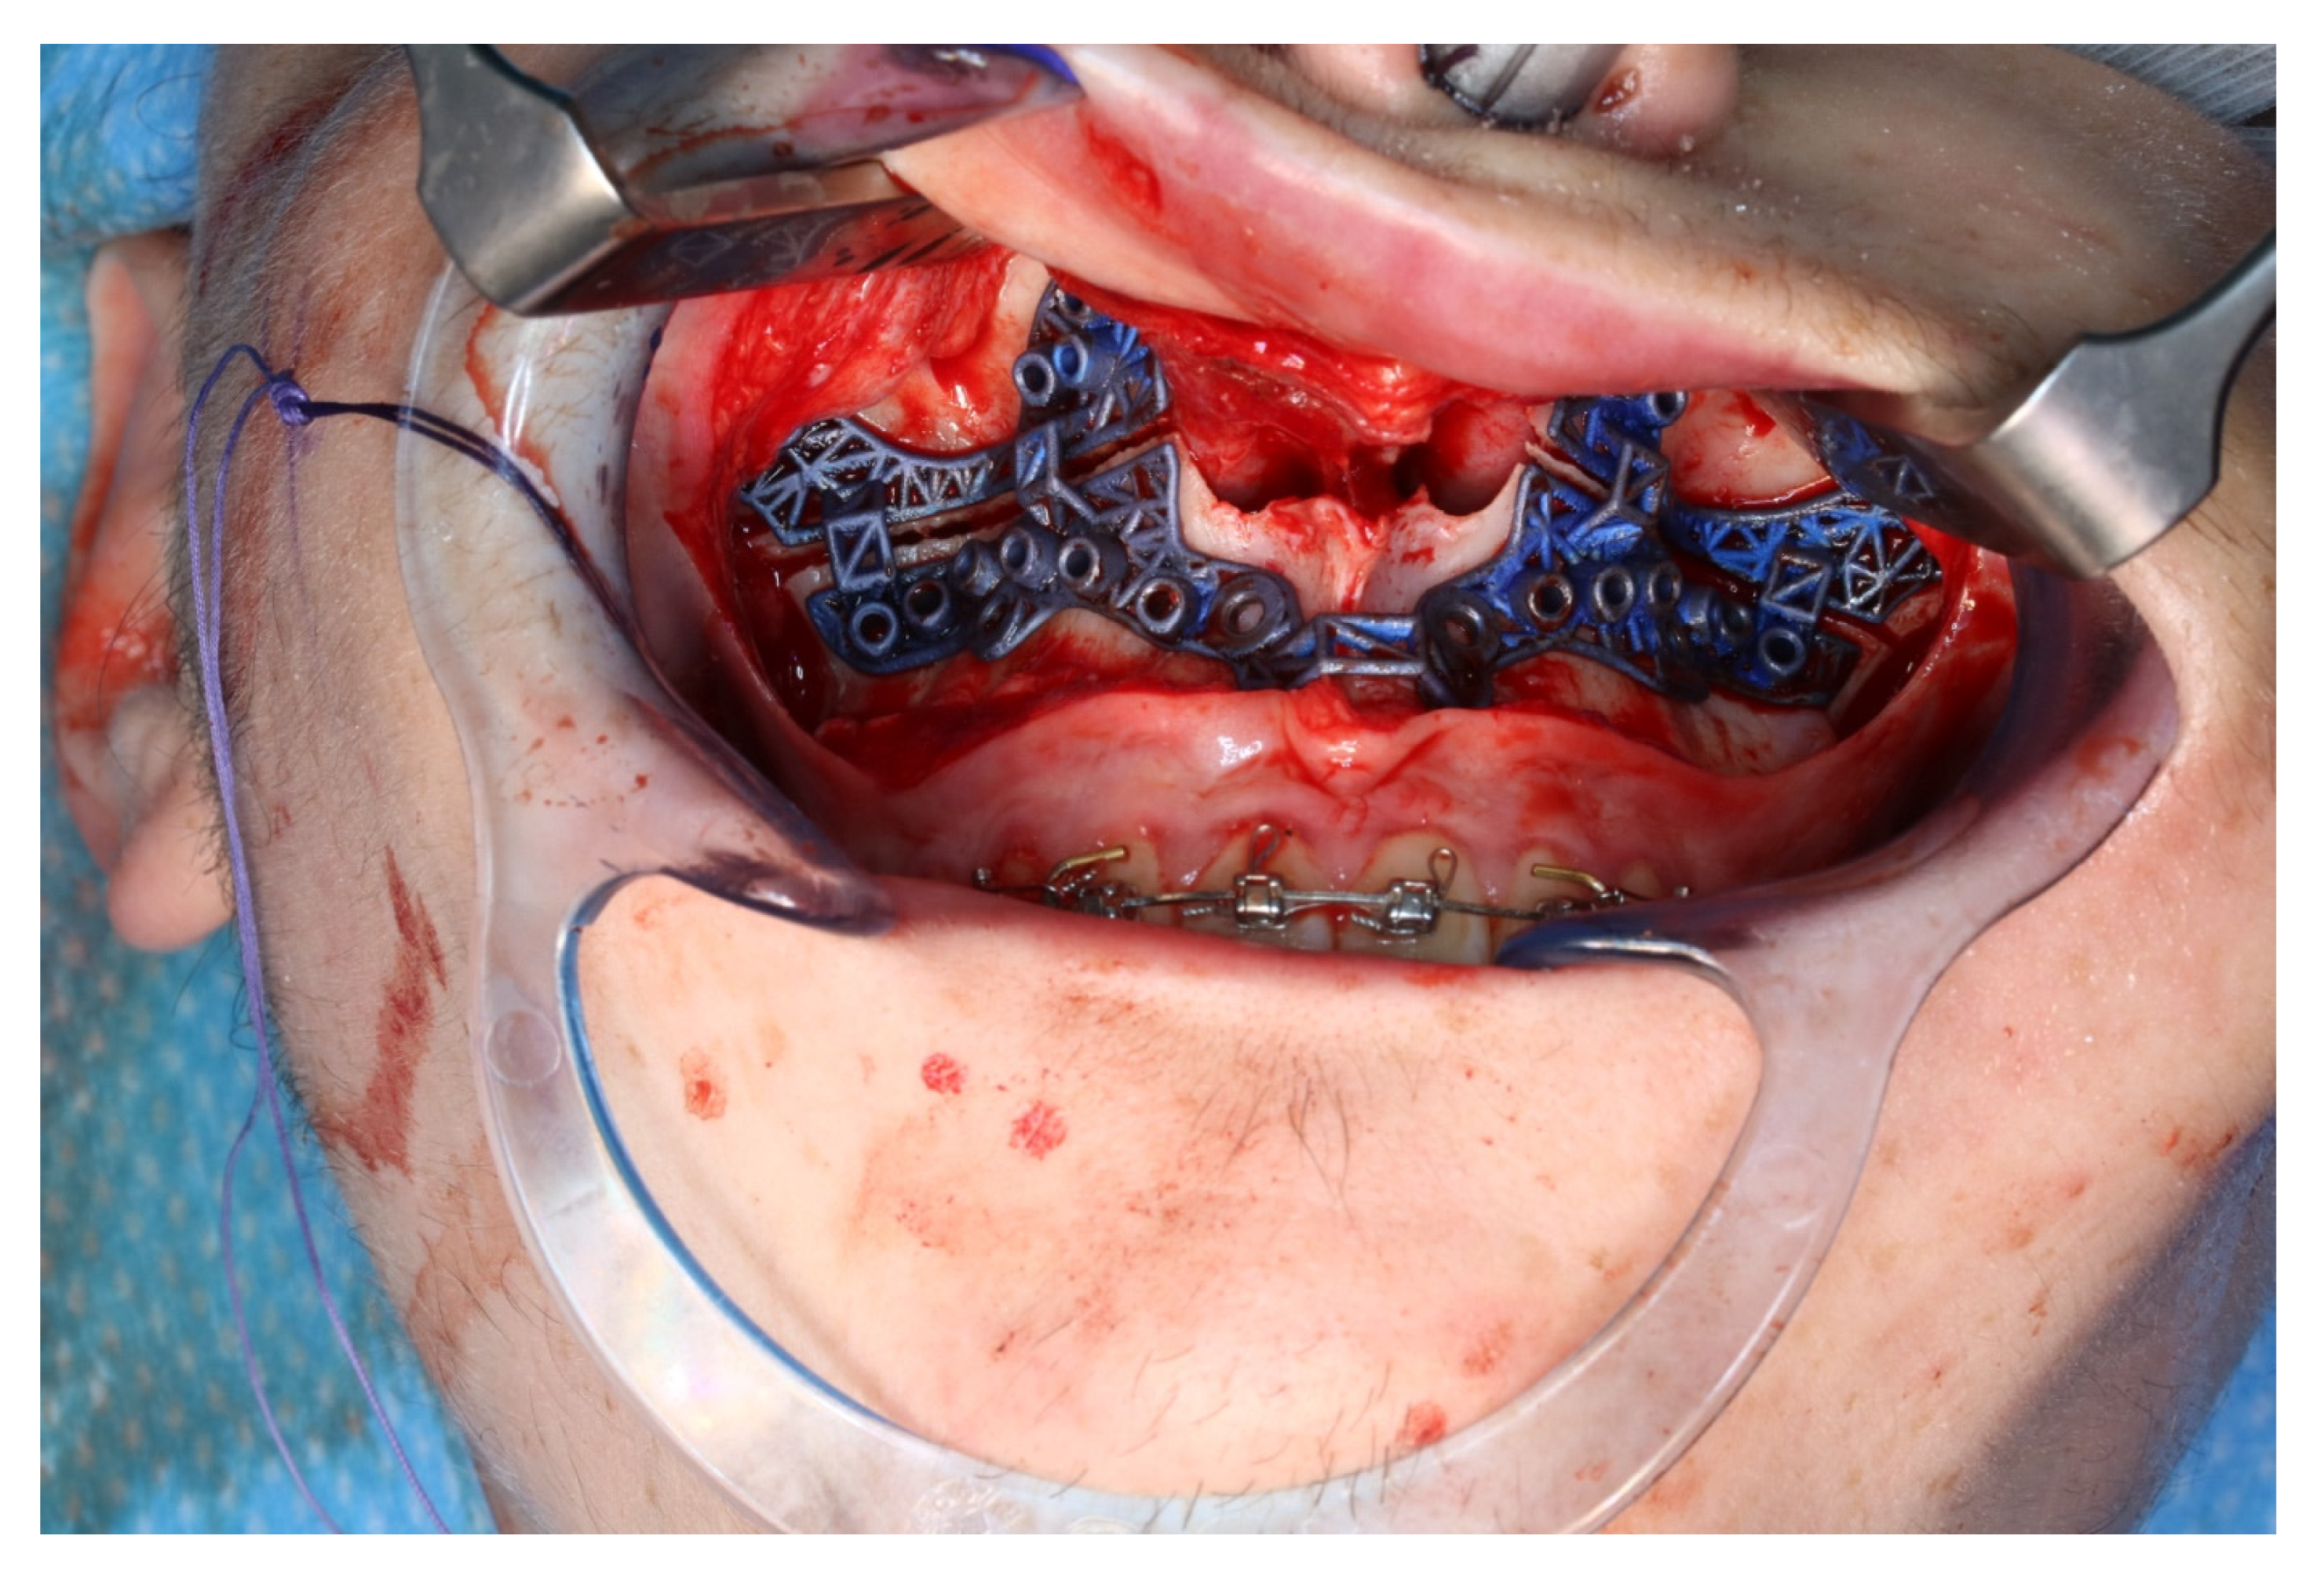

Figure 11.

Upper jaw positioned and fixed by means of patient-specific implant.